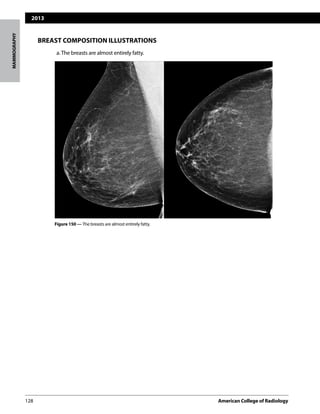

a.The breasts are almost entirely fatty.

Figure 150 — The breasts are almost entirely fatty.